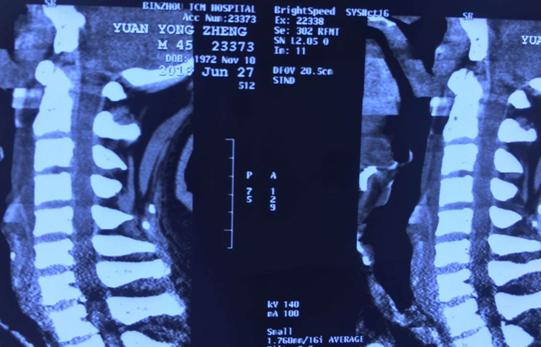

术前CT

术后CT